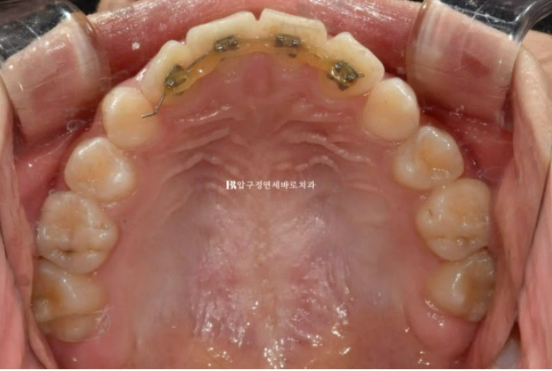

장치 제작에 들어갔고 23년 9월부터 드디어 첫 세트의 1단계 장치를 끼기 시작했습니다.

왼쪽 위 어금니를 앞으로 끌어오기 위해서 잇몸에 교정용 미니스크류도 심고 뺏다꼈다 하는 고무줄도 쓰면서 진행했습니다.

재제작 후 추가장치에서는 작은어금니를 뿌리까지 평행하게 땡겨오기 위한 장치가 추가되었습니다.